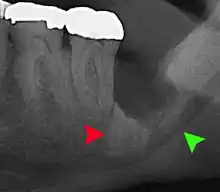

Impacted wisdom tooth with a backward tilt (distoangular impaction) and chronic infection to back of crown (green arrow)

Coronectomy of impacted wisdom tooth post-op xray showing root remnants (red arrow) and inferior alveolar nerve (green arrow)

Coronectomy is a procedure where the crown of the impacted wisdom tooth is removed, but the roots are intentionally left in place. It is indicated when there is no disease of the dental pulp or infection around the crown of the tooth, and there is a high risk of inferior alveolar nerve injury.[31]

Coronectomy, while lessening the immediate risk to the inferior alveolar nerve function has its own complication rates and can result in repeated surgeries. Between 2.3% and 38.3% of roots loosen during the procedure and need to be removed and up to 4.9% of cases require reoperation due to persistent pain, root exposure or persistent infection. The roots have also been reported to migrate in 13.2% to 85.9% of cases.[31]